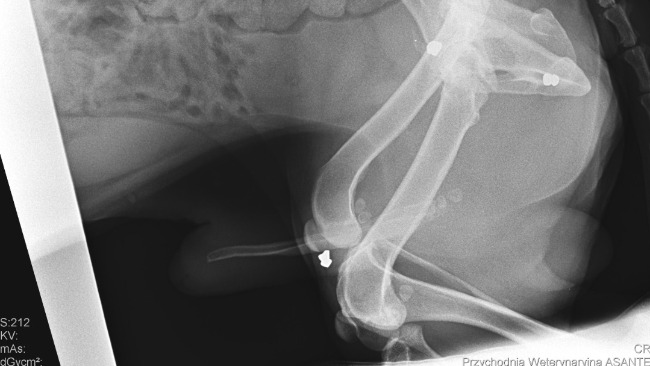

Ostatnie wizyty u specjalistów kompletnie mnie rozwaliły. U ortopedy prześwietlenia wykazały silne zmiany zwyrodnieniowe prawie wszystkich stawów, w tym te niezwykłe bolesne w bioderkach oraz zwichnięcie rzepki. Dlatego Jogi ma takie problemy z chodzeniem.

Ale na zdjęciach zobaczyłam coś znacznie gorszego, co rozwaliło mi serce na miliony kawałków. Ten biedak jest cały nafaszerowany śrutem. Jakiś zwyrodnialec strzelał do niewidomego psiaka, który nie wiedział, z której strony padały strzały i nawet nie był w stanie uciekać. CZY MOŻECIE WYOBRAZIĆ SOBIE TEN STRACH I CIERPIENIE ???!!!!!!!!!!!!!!!!!!!!! Jakim trzeba być zwyrolem i zarazem tchórzem, żeby strzelać do kalekiego, niewidomego zwierzaka.